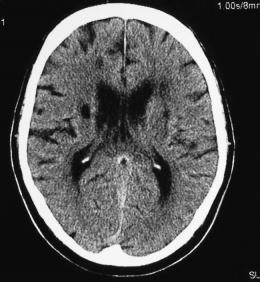

Una apoplejía menor, o ataque isquémico transitorio (AIT), es una interrupción breve del flujo sanguíneo a alguna parte del cerebro. Los síntomas pueden durar tan sólo unos minutos o algunas horas y no resultan en incapacidad a largo plazo, pero estudios anteriores han mostrado que estos infartos pueden ser señales de alarma para condiciones más severas.